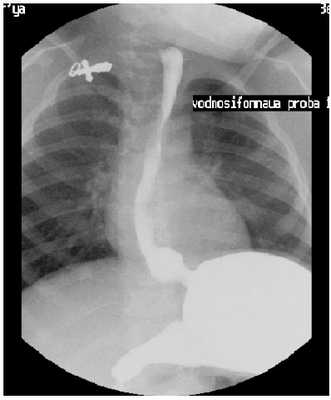

Следующий этап, при отрицательных результатах выше выполненных манипуляций, постановка водно-сифонной пробы.

Пациент укладывается на спину в положении на правом боку под углом 450 [2], указание на методику, предложенную Linsman в 1965 г.). Положительным считается проба, при которой происходит заброс содержимого желудка в пищевод. При этом можно осуществлять маятникообразные умеренные надавливания на переднюю брюшную стенку, для оценки состояния средне пищеводного сфинктера [3, 4, 5].

Высока значимость водно-сифоной пробы (ВСП), при установлении ГЭР. Из 50 обследованных детей по поводу ГЭР, заброс без ВСП регистрировался у 19-и (методика Singleton - контраст вводится в расчёте 1/3 от разового кормления), и у 32-х, при выполнении ВСП [2].